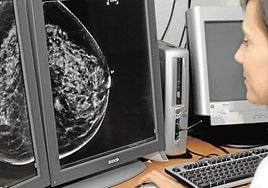

La Fiscalía de Sevilla archiva la denuncia de AMAMA por la supuesta alteración de historiales médicos

La investigación avala la versión de la Junta y concluye que la caída del sistema no afectó al contenido de los expedientes